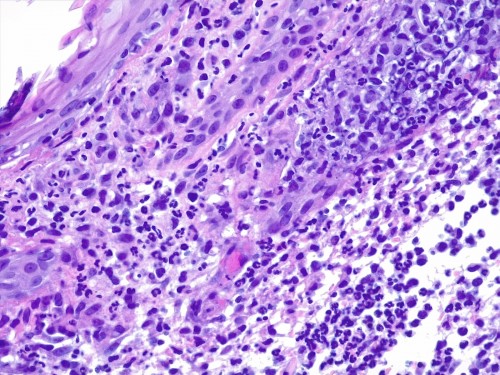

– les biopsies cutanées (LAPVSO) concluent à de sévères lésions de dermohypodermite neutrophilique avec furonculose et lésions hypodermiques ponctuelles de vascularite leucocytoclasique (Photos 4 à 9)

Examen histopathologique montrant un épiderme intact ou sévèrement ulcéré. Dans le derme, on observe un œdème superficiel ainsi que de multiples foyers inflammatoires non encapsulés, souvent à point de départ folliculaire ou périfolliculaire, pouvant fusionner, rompre les follicules pileux et s’étendre dans l’ensemble du derme voire gagner l’hypoderme. Ces foyers sont caractérisés par l’accumulation de granulocytes neutrophiles qui semblent altérés et qui dissèquent les fibres de collagène autour du follicule pileux ainsi que la paroi folliculaire et la lumière folliculaire. De nombreuses plages inflammatoires contiennent des tiges pilaires nues. L’infiltrat peut s’étendre dans l’hypoderme, mais ce dernier est surtout caractérisé par un épaississement des septa conjonctifs interlobulaires du tissu adipeux avec œdème, accumulation d’un matériel fibrinoïde, dilatation vasculaires des vaisseaux lymphatiques et des structures vasculaires de petit calibre, les vaisseaux lymphatiques étant encombrés d’un matériel inflammatoire fibrino-leucocytaire. Il peut exister des images focales de vascularite leucocytoclasique au sein de l’hypoderme.